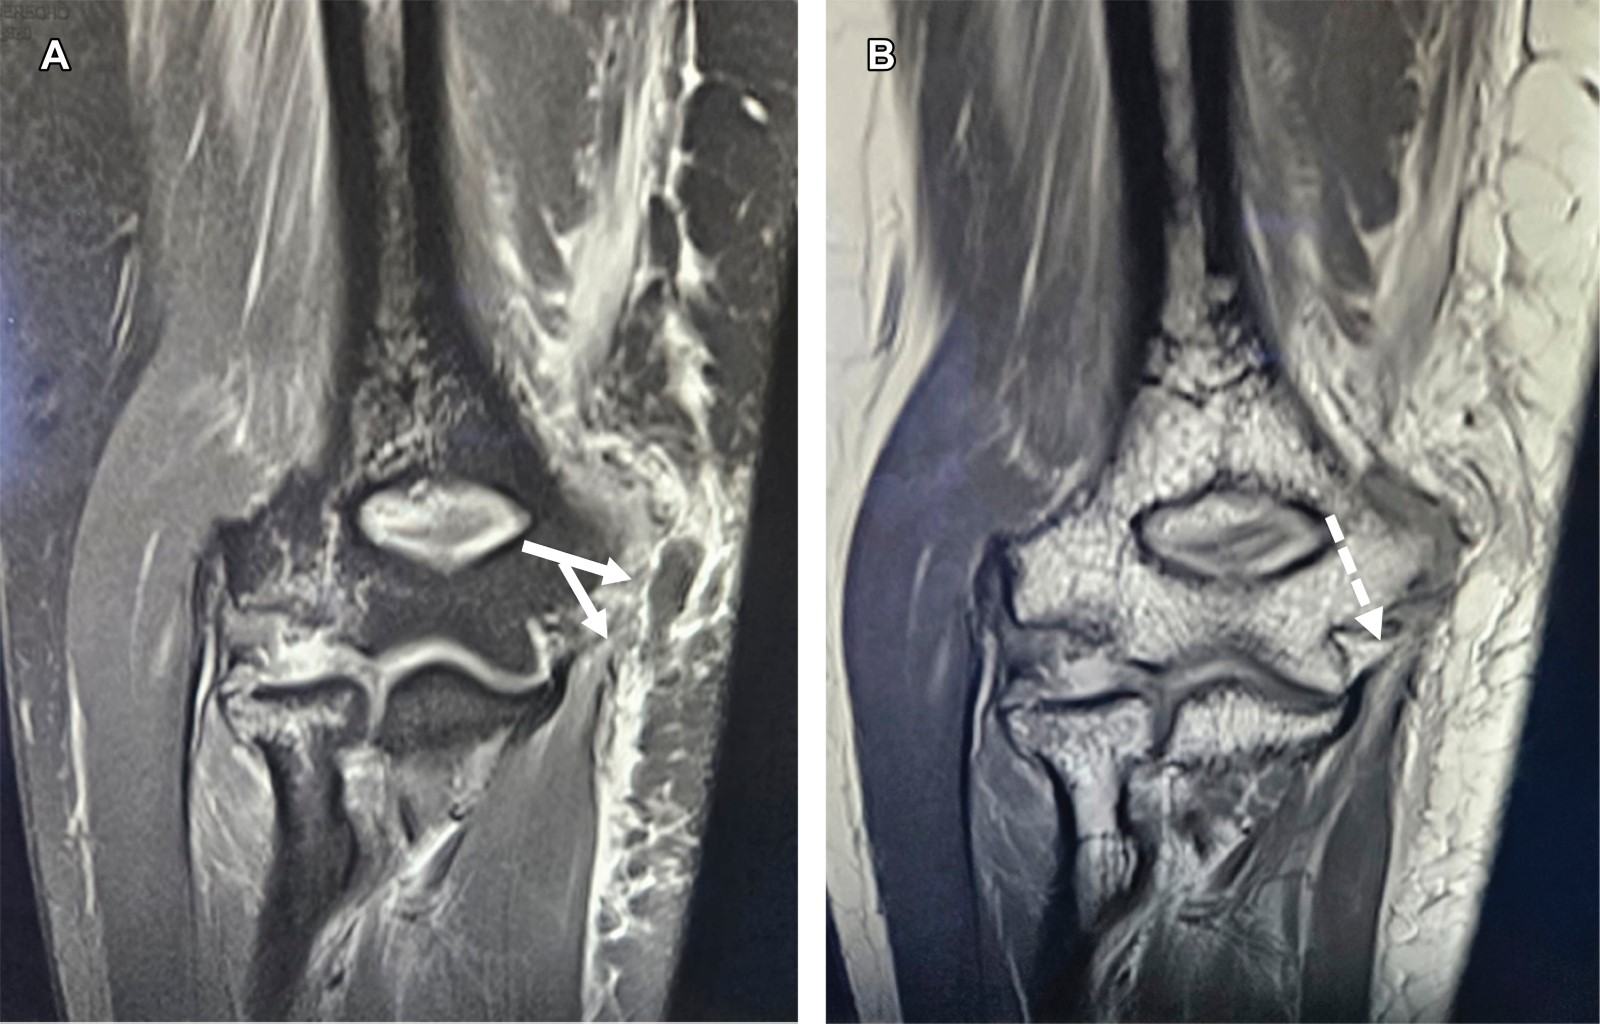

A la exploración dirigida se encuentra edema de codo, limitación para la flexión de los dedos, del carpo y ausencia de pronosupinación, sensibilidad conservada para nervios mediano y radial, hipoestesia en territorio del nervio cubital, con paresia 2/5 de músculos abductor, flexor corto y oponentes del quinto dedo. Con diagnóstico de probable fractura epitroclear se efectúa resonancia magnética (Figuras 1 y 2), la cual mostró: líneas de fracturas no desplazadas del capitellum humeral y de cabeza radial y edema óseo, fractura avulsión de epitróclea con desprendimiento de las inserciones del pronador redondo, palmar mayor, palmar menor, cubital anterior y flexor común superficial de los dedos, además de desprendimiento del ligamento anterior en su porción medial y del ligamento colateral medial del codo, incluyendo su fascículo posterior (ligamento de Bardinet), así como de la inserción medial del ancóneo, ruptura parcial del braquial anterior, hematoma en cara antero medial con extensión al compartimiento braquial posterior.

Figura 1